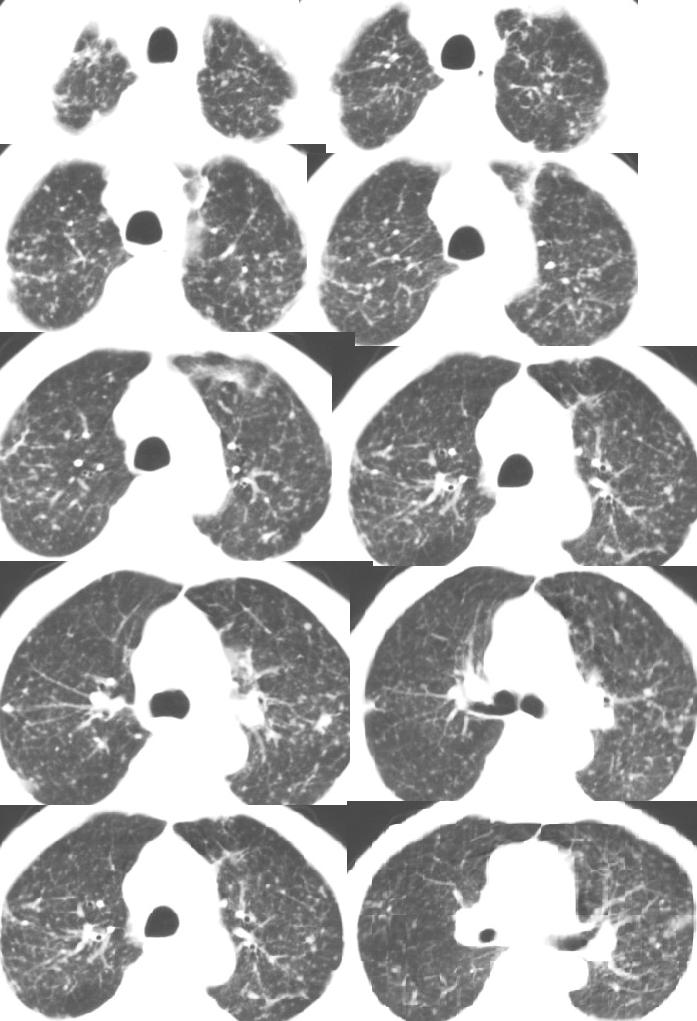

以下是引用医影拾贝在2008-6-3 18:48:00的发言:[br]双上肺弥漫性小结节影,纵隔窗内钙化淋巴结影,考虑血播性tb可能性较大,不除外肺ca可能

以下是引用jinguoji在2008-6-3 20:20:00的发言:[br]双上肺弥漫性小结节影,纵隔窗内钙化淋巴结影,考虑血播性tb可能性较大,不除外肺ca可能。腰椎考虑退变。

以下是引用卜一在2008-6-3 19:33:00的发言:[br]双肺结节,以双上肺分布为多,期间搀杂片状致密影及索条致密影。考虑:继发性肺结核伴血型播散可能性大。不除外肺泡ca的可能!另:椎体退变!

以下是引用panyishengct在2008-6-3 21:09:00的发言:[br]双上肺弥漫性小结节影,纵隔窗内钙化淋巴结影,考虑矽肺或/和tb可能性较大,不除外肺ca可能。腰椎考虑退变。 [br][br]